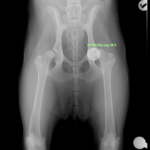

若齢のゴールデン・レトリーバーの股関節形成不全(CHD)に対し、人工股関節全置換術(THR)を実施しました。術前のエックス線では、両側に顕著な股関節亜脱臼を認めましたが、重度の変形性関節症は認められていません。亜脱臼が顕著であることから関節温存のための3Dhip/DPO/TPOは不適応と判断しました。

今回、選択したインプラント

• Acetabular Cup:26.5 mm

• Femoral Stem:Size M/Neck Short/Head19mm